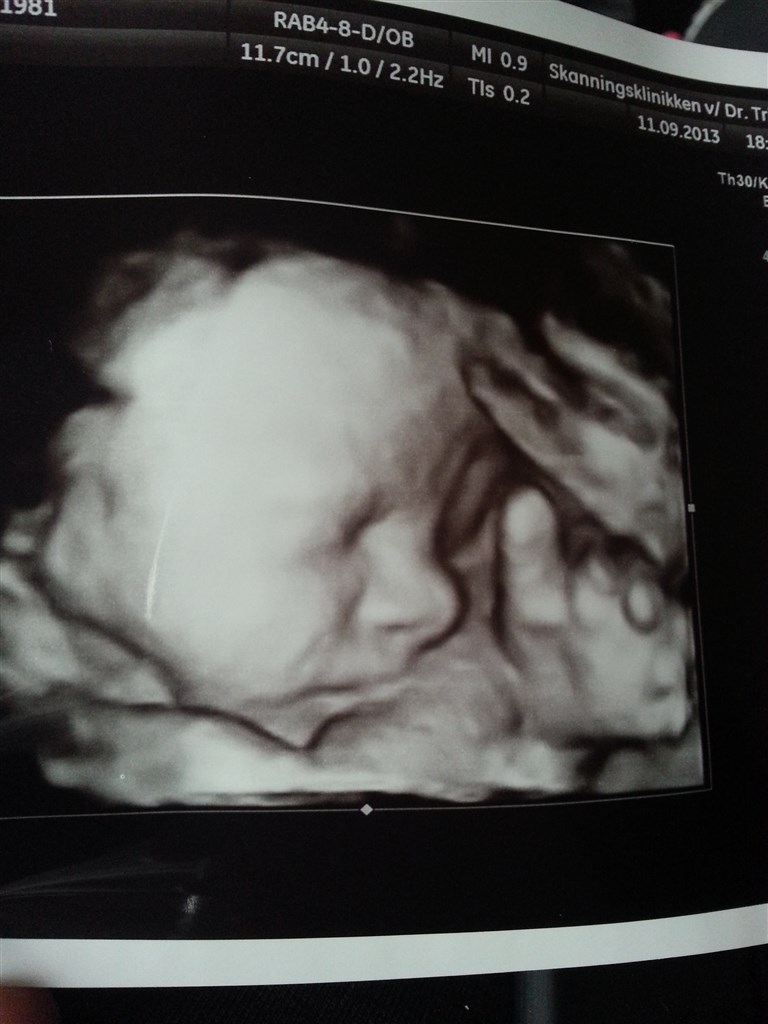

Fra hvilken uge er det værd at få en 3D/4D scanning ?

Efter uge 12 eller ?

Det kommer an på mange ting, men mellem 21-32 tror jeg man siger

Min moderkage ligger foran så der hed det før uge 28, vi var afsted 26+6 og det var en fantastisk oplevelse

.. Men ville heller ikke gøre det før der, så har baby ikke så meget fedt på kroppen og har derfor ikke så mange personlige træk